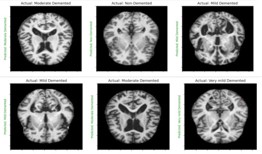

Model training

Python code has been used for the training and testing process. The code contains several libraries such as tensorflow, numpy, matplotlib, keras which is a higher-level neural networks API that comes integrated with tensorflow [1]. The loading of the training and test datasets is done using tf.keras.preprocessing.image_dataset_from_directory(). A neural network model with multiple layers is created using keras that contains convolutional, Max-pooling, Dropout and Dense layers. Sparse categorical cross-entropy loss function and Adam optimizer are used to build the model. The training process is run for 35 epochs as shown in figure 8. The loss and accuracy gained is plotted and the visualization of the test images and predictions are made which was displayed in figure9. Finally, the trained model is stored as “ALZ.h5 ‘’ in HDF5 format [12].

Results and discussion

Image preprocessing and feature extraction is done based on the brightness, texture, dimension etc. Using thresholding, Augmentation, Gray scaling [13]. DL techniques and algorithms have been used for training the model, identification and classification of the Image. The results show that the trained model produces 98.02% accuracy in the prediction of the disease and classification is given as output when the input, that is MRI of the Brain is fed to the system.